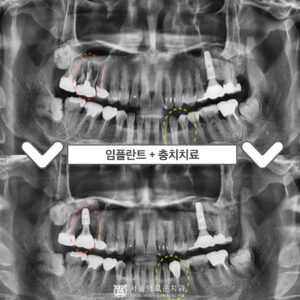

부천서울이로운치과 과거에 치료받았던 보철이 불편하다면? 안녕하세요! 부천서울이로운치과 대표원장 이경중입니다 🙂 앞니는 어금니와 달리 우리가 말할 때나 음식을 먹거나 미소를 지을 때 외부로 드러나 보이는 부분이기 때문에 심미적인 부분에서도 중요한 부분을 차지하게 되는데요. 그렇게 때문에 적절하지 못한 보철물로 인해 보기 좋지 않거나, 잇몸 건강에 문제가 있는 경우 재보철을 통해 더보기…